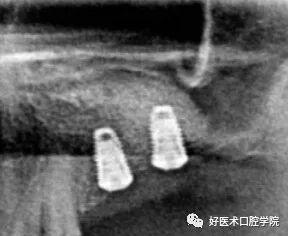

1)术前CBCT测量:术前测量上颌窦底壁到牙槽嵴顶距离、上颌窦底壁到囊肿边缘的距离以及测量设计骨开窗位置。

2)鼓起实验、抽取囊液

3)分离囊壁、缝合上颌窦黏膜

4)骨增量缝合